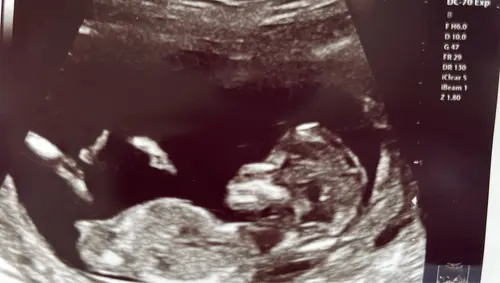

Kan je toevallig hierin wel wat zien haha?

Deze had je keertje al geposted hihi, ik denk wel jongen

Ah oké! Deze foto’s waren met 13+2